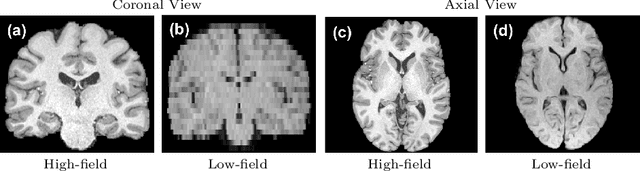

Abstract:Low-field (LF) MRI scanners (<1T) are still prevalent in settings with limited resources or unreliable power supply. However, they often yield images with lower spatial resolution and contrast than high-field (HF) scanners. This quality disparity can result in inaccurate clinician interpretations. Image Quality Transfer (IQT) has been developed to enhance the quality of images by learning a mapping function between low and high-quality images. Existing IQT models often fail to restore high-frequency features, leading to blurry output. In this paper, we propose a 3D conditional diffusion model to improve 3D volumetric data, specifically LF MR images. Additionally, we incorporate a cross-batch mechanism into the self-attention and padding of our network, ensuring broader contextual awareness even under small 3D patches. Experiments on the publicly available Human Connectome Project (HCP) dataset for IQT and brain parcellation demonstrate that our model outperforms existing methods both quantitatively and qualitatively. The code is publicly available at \url{https://github.com/edshkim98/DiffusionIQT}.

Abstract:Low-field (<1T) magnetic resonance imaging (MRI) scanners remain in widespread use in low- and middle-income countries (LMICs) and are commonly used for some applications in higher income countries e.g. for small child patients with obesity, claustrophobia, implants, or tattoos. However, low-field MR images commonly have lower resolution and poorer contrast than images from high field (1.5T, 3T, and above). Here, we present Image Quality Transfer (IQT) to enhance low-field structural MRI by estimating from a low-field image the image we would have obtained from the same subject at high field. Our approach uses (i) a stochastic low-field image simulator as the forward model to capture uncertainty and variation in the contrast of low-field images corresponding to a particular high-field image, and (ii) an anisotropic U-Net variant specifically designed for the IQT inverse problem. We evaluate the proposed algorithm both in simulation and using multi-contrast (T1-weighted, T2-weighted, and fluid attenuated inversion recovery (FLAIR)) clinical low-field MRI data from an LMIC hospital. We show the efficacy of IQT in improving contrast and resolution of low-field MR images. We demonstrate that IQT-enhanced images have potential for enhancing visualisation of anatomical structures and pathological lesions of clinical relevance from the perspective of radiologists. IQT is proved to have capability of boosting the diagnostic value of low-field MRI, especially in low-resource settings.

Abstract:1.5T or 3T scanners are the current standard for clinical MRI, but low-field (<1T) scanners are still common in many lower- and middle-income countries for reasons of cost and robustness to power failures. Compared to modern high-field scanners, low-field scanners provide images with lower signal-to-noise ratio at equivalent resolution, leaving practitioners to compensate by using large slice thickness and incomplete spatial coverage. Furthermore, the contrast between different types of brain tissue may be substantially reduced even at equal signal-to-noise ratio, which limits diagnostic value. Recently the paradigm of Image Quality Transfer has been applied to enhance 0.36T structural images aiming to approximate the resolution, spatial coverage, and contrast of typical 1.5T or 3T images. A variant of the neural network U-Net was trained using low-field images simulated from the publicly available 3T Human Connectome Project dataset. Here we present qualitative results from real and simulated clinical low-field brain images showing the potential value of IQT to enhance the clinical utility of readily accessible low-field MRIs in the management of epilepsy.

Abstract:MR images scanned at low magnetic field ($<1$T) have lower resolution in the slice direction and lower contrast, due to a relatively small signal-to-noise ratio (SNR) than those from high field (typically 1.5T and 3T). We adapt the recent idea of Image Quality Transfer (IQT) to enhance very low-field structural images aiming to estimate the resolution, spatial coverage, and contrast of high-field images. Analogous to many learning-based image enhancement techniques, IQT generates training data from high-field scans alone by simulating low-field images through a pre-defined decimation model. However, the ground truth decimation model is not well-known in practice, and lack of its specification can bias the trained model, aggravating performance on the real low-field scans. In this paper we propose a probabilistic decimation simulator to improve robustness of model training. It is used to generate and augment various low-field images whose parameters are random variables and sampled from an empirical distribution related to tissue-specific SNR on a 0.36T scanner. The probabilistic decimation simulator is model-agnostic, that is, it can be used with any super-resolution networks. Furthermore we propose a variant of U-Net architecture to improve its learning performance. We show promising qualitative results from clinical low-field images confirming the strong efficacy of IQT in an important new application area: epilepsy diagnosis in sub-Saharan Africa where only low-field scanners are normally available.